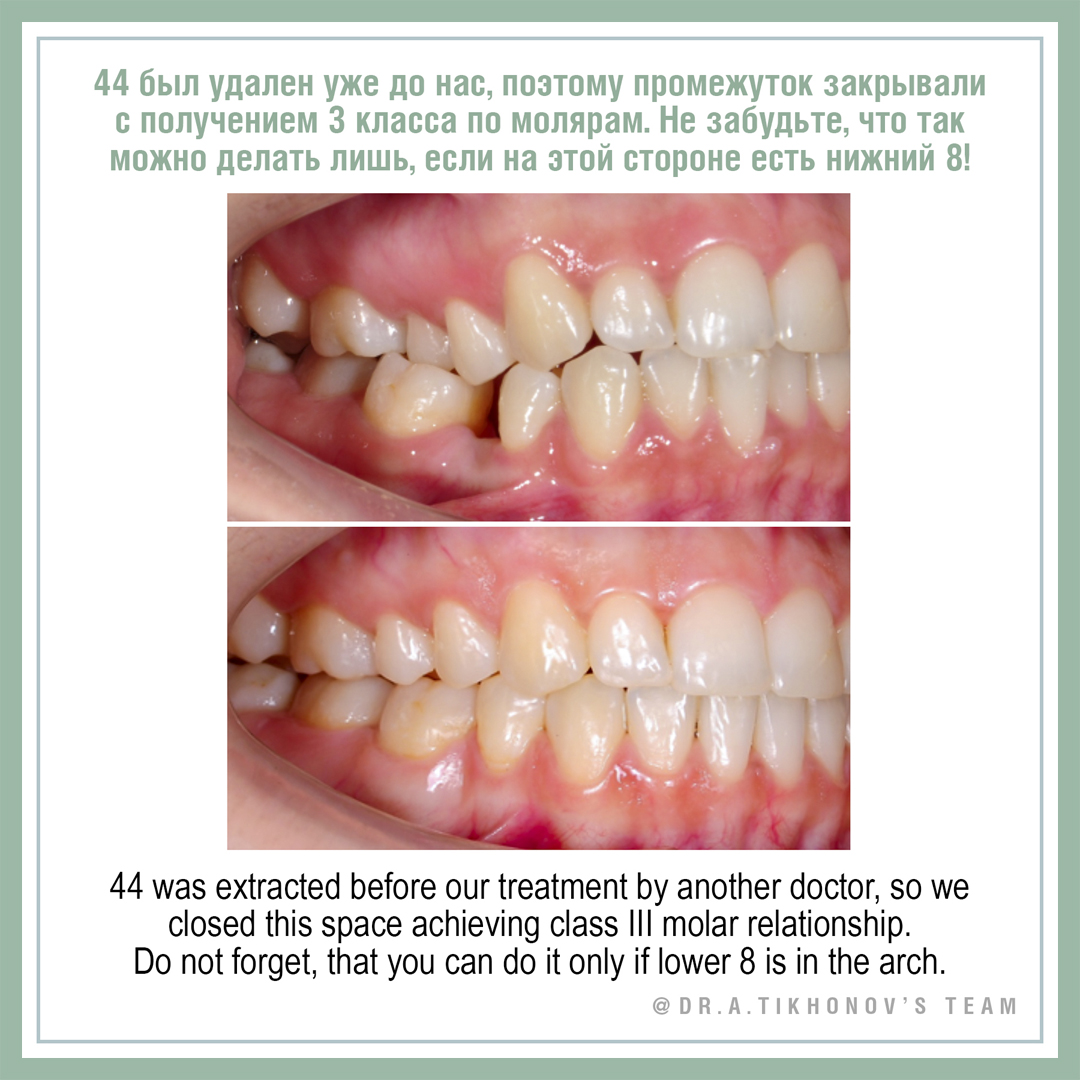

44 был удален уже до нас, поэтому промежуток закрывали с получением 3 класса по молярам.

Не забудьте, что так можно делать лишь, если на этой стороне есть нижний 8!

Smile arc and curve of Spee correction by posterior intrusion with TADs. Gummy smile in posterior segments corrected. 44 was extracted before our treatment by another doctor, so we closed this space achieving class III molar relationship. Do not forget, that you can do it only if lower 8 is in the arch.